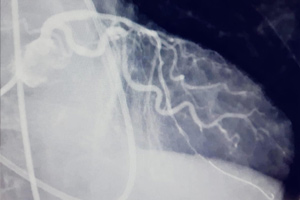

Intervención coronaria percutánea

Por vía telerrobótica remota